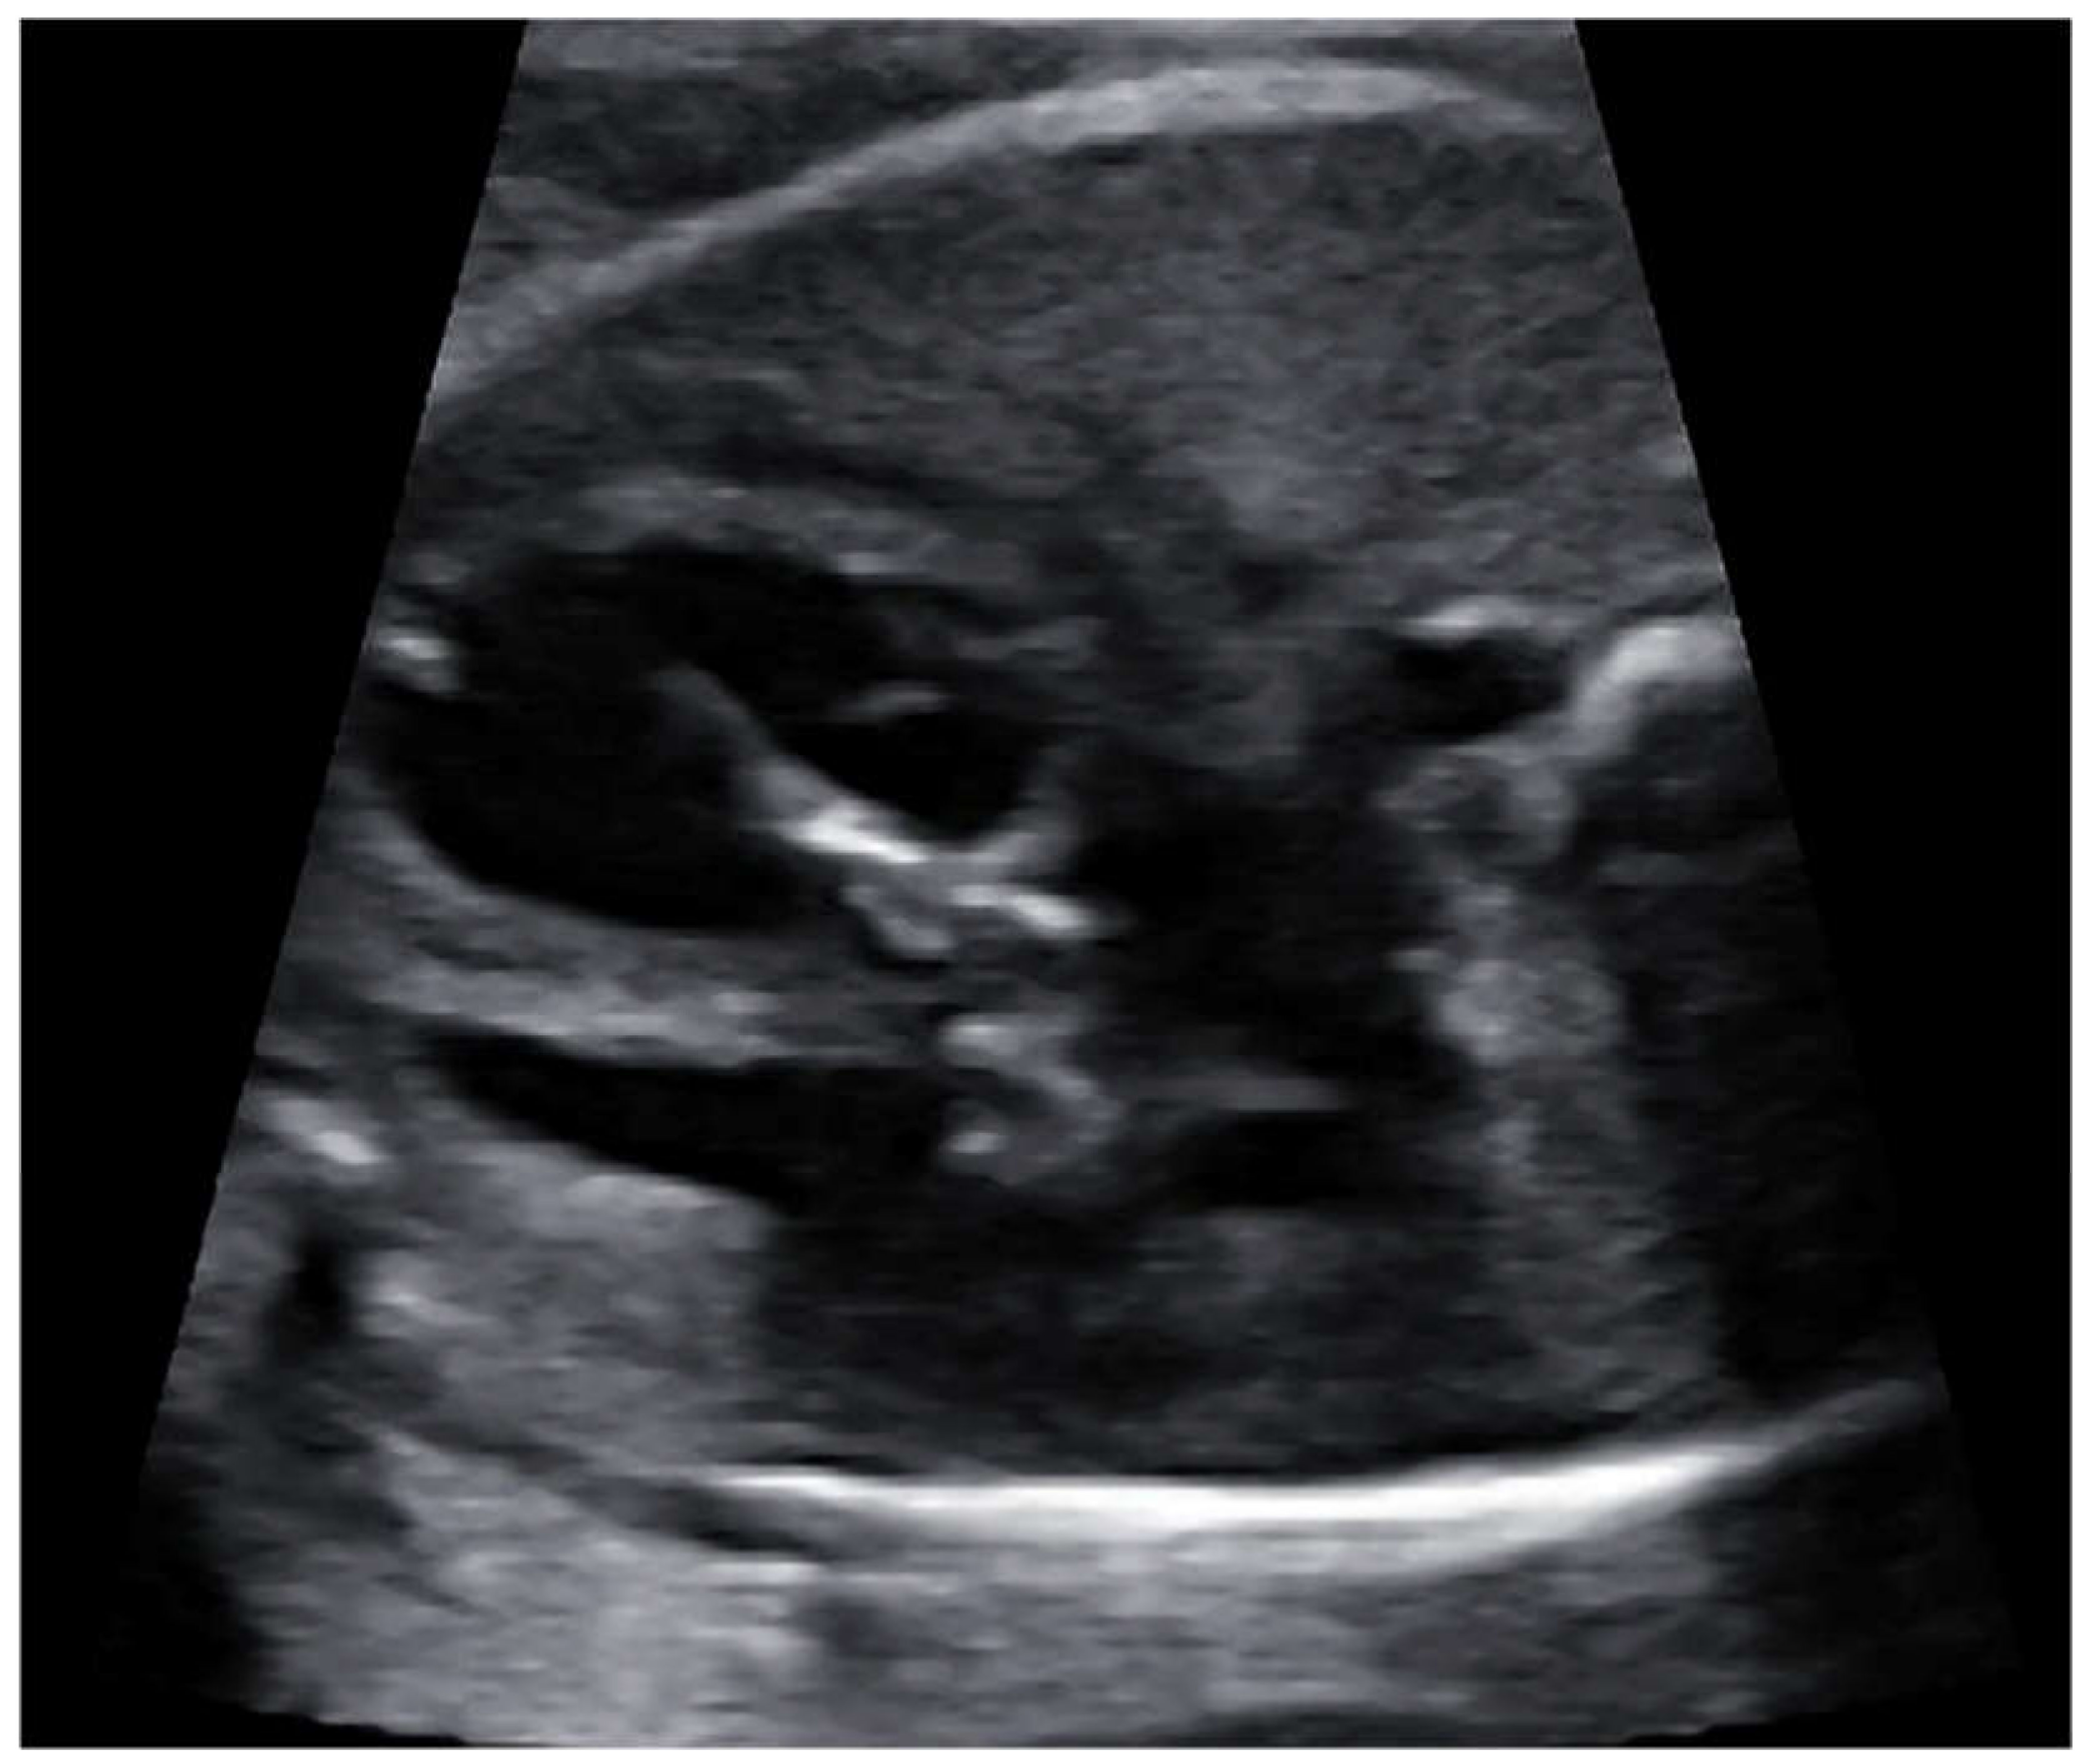

Fetal balloon aortic valvuloplasty (fBAV) was considered successful when the balloon crossed the aortic valve, was inflated and deflated at least three times, and forward flow through the aortic valve was larger than before the procedure (Figure 4). Aortic insufficiency was the additional sign that the valve was dilated, however, its appearance was not necessary to consider the procedure successful.

Figure 4.

fBAV—the coronary balloon inflated in the aortic valve. The left ventricular apex was punctured and the needle with the coronary balloon was introduced through the aortic valve.